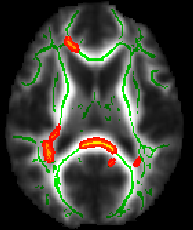

The script finishes by telling you to check whether a suitable threshold for the mean FA skeleton is 0.2 (a typical value used by the next script). For example, load the 4D FA data and the skeleton into FSLView:

cd stats

fsleyes all_FA -dr 0 0.8 mean_FA_skeleton -dr 0.2 0.8 -cm green

The -dr option sets sensible display range options, and in the case of the skeleton image, also controls the thresholding applied. Now turn on the movie loop; you will see the mean FA skeleton on top of each different subject's aligned FA image. If all the processing so far has worked ok the skeleton should look like the examples shown here (see the TBSS paper for more examples of different subjects' results underneath the skeleton). If the registration has worked well you should see that in general each subject's major tracts are reasonably well aligned to the relevant parts of the skeleton. If you set the skeleton threshold (in FSLeyes, the lower of the display range settings) much lower than 0.2, it will extend away towards extremes where there is too much cross-subject variability and where the nonlinear registration has not been able to attain good alignments. Remember the skeleton threshold for the next stage.